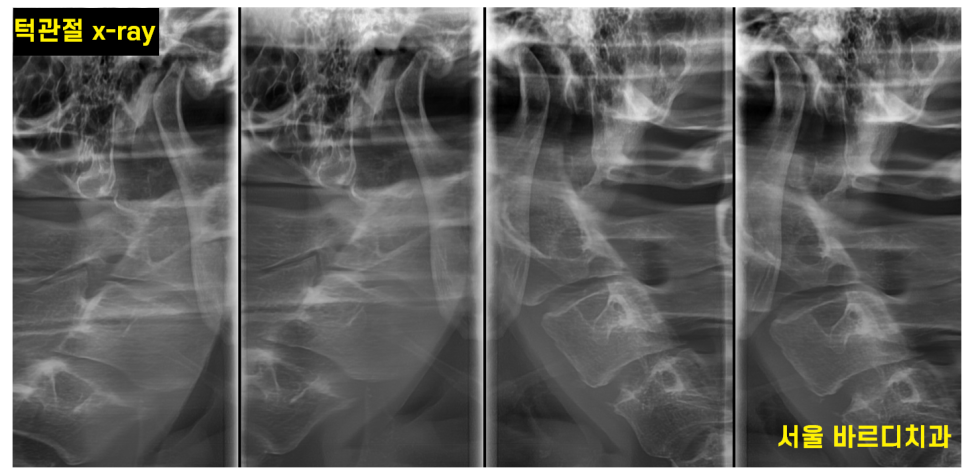

턱관절만 확인할 수 있는 x-ray 촬영도 가능합니다!

증상에 따라 약 처방, 보톡스, 물리치료, 장치 치료

적절한 처방을 해드리겠습니다~~